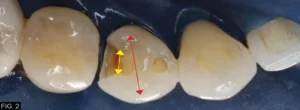

The carious lesion was rather deep into the tooth according to the radiographic image but not wide. The carious lesion was less than ½ the distance between the buccal/lingual cusp distance making this an excellent case for a direct composite restoration. (FIG. 2)

However, a cross section of the occlusal theme of tooth #28 (#44) commonly has two planes connecting both buccal/lingual cusp tips into the central groove and both mesial/distal fossae as indicated with the red and yellow lines which must be taken into consideration. (FIG.12)

The red and yellow lines highlight the two-plane occlusal form of tooth #28 (#44), connecting the buccal and lingual cusp tips to the central groove and mesial/distal fossae.

The proper occlusal anatomy of any posterior tooth can be created with a simple flame shaped fine diamond bur (Komet® FG8888) which will allow you to carve the two planes that make up the triangular ridges while following the occlusal pattern of a particular posterior tooth as seen with this patient. (FIG.13) The tip of the bur is used to develop the fossa and steeper planes (red) and the remaining tooth structure will guide your less steep plane (yellow) development.